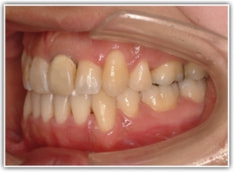

治療後(2年3ヶ月後)

舌位、気道、咽頭扁桃、口蓋扁桃、良好なEラインとプロファイルが得られております。

歯根のパラレリング(平行性)が獲得されております。

下顎8番は、両側抜歯済みです。